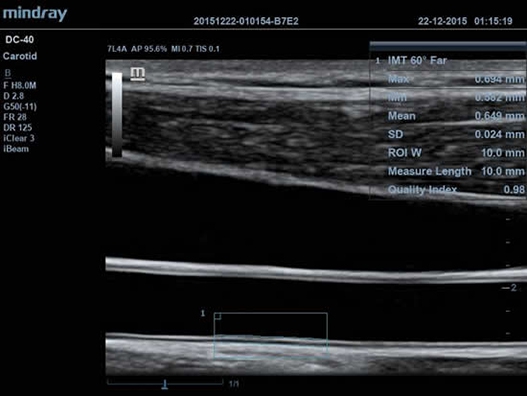

• Функция Auto IMT автоматически измеряет толщину комплекса интима-медиа.

• Auto IMT Package – измерения и анализ толщины комплекса интимамедии (КИМ) сонной артерии;

• Высокочастотный линейный датчик 38 мм Mindray l14-6NE